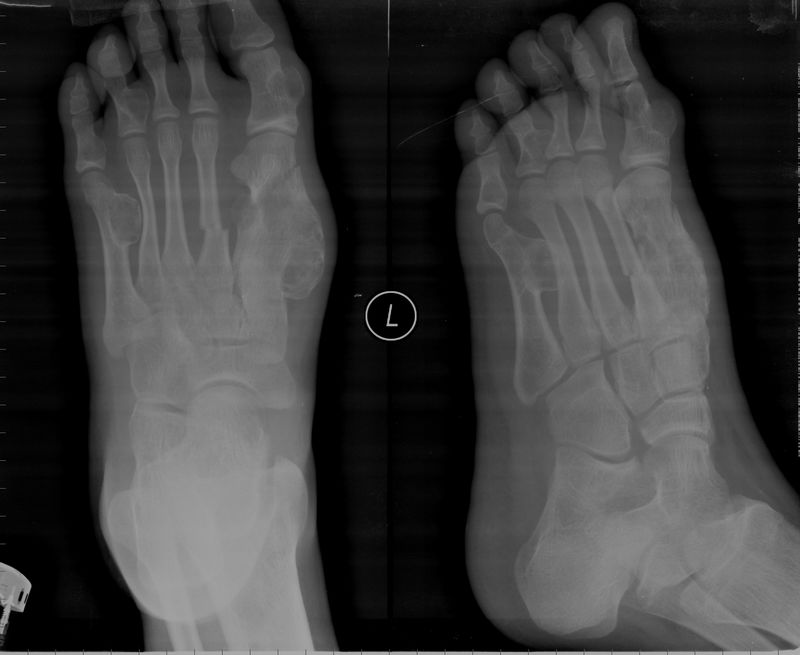

男,13岁,发现左足多发包块5年,因外伤来诊,右足多趾畸形,请大家会诊,谢谢。过几天手术做病理

1、左足多发骨旁骨瘤;2、左侧第一、二謶骨骨折。

多发软骨瘤(内生+外生),1、2跖骨骨折。

支持:多发软骨瘤(内生+外生),1、2跖骨骨折。

软骨瘤,不是骨软骨瘤,一字之差,谬之千里。

多发内生软骨瘤伴病理性骨折